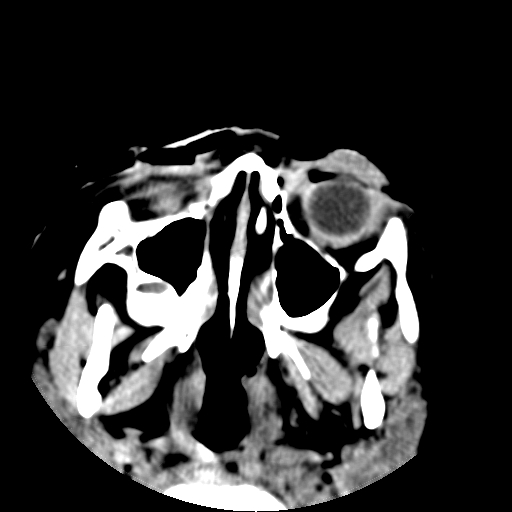

以下是引用深泽交通医院在2009-10-16 8:25:00的发言:[br]右眼环出血伴异物

以下是引用卜一在2009-10-16 15:01:00的发言:[br]右眼球挫裂伤伴异物!

以下是引用拾荒者在2009-10-17 18:38:00的发言:[br]鼻面部皮下积气,右侧睑缘及眼球壁高密度异物影,左侧眼球壁晶状体内侧缘处是圆形低密度影。低密度异物?应提请眼科医生注意。